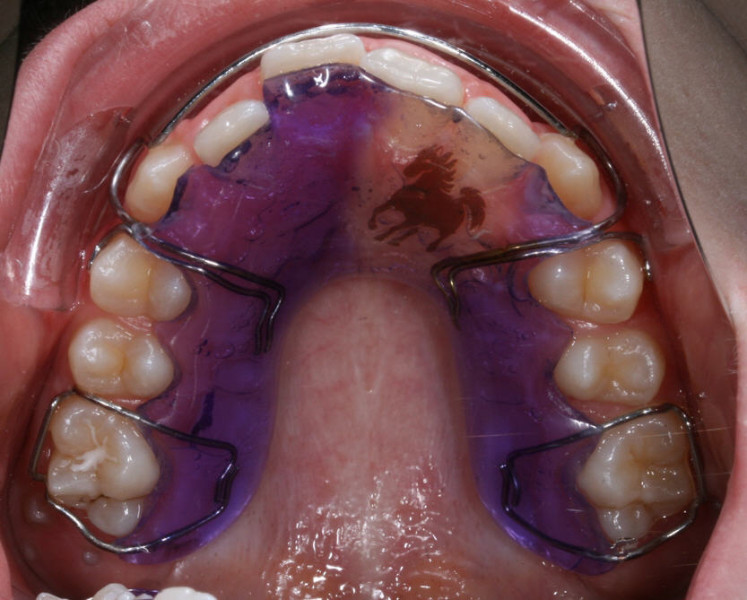

Lose Spangen dienen entweder als aktive Behandlungsapparaturen z.B. zur Frühbehandlung oder als passive Apparaturen zum Halten des erreichten Behandlungsergebnisses.

Als Teil der aktiven Behandlung, dienen sie z.B. entweder zur Korrektur der Zahnbögengröße  und -Form oder des Verhältnisses zwischen Ober- und Unterkiefer.

Die rechtzeitige Anwendung solche Geräte gibt dem Kieferorthopäden die Möglichkeit das Wachstum des Kiefers in die optimale Richtung zu lenken.